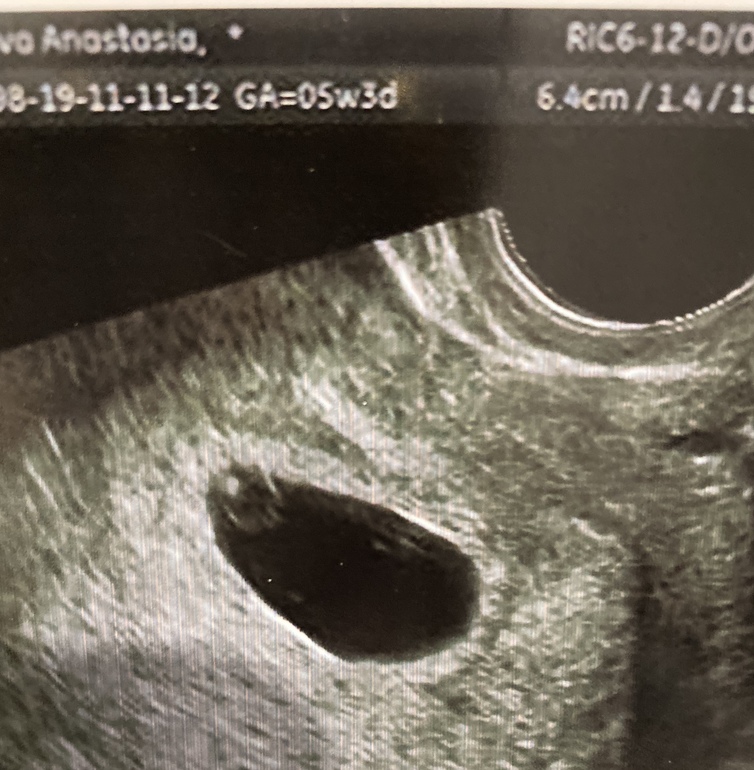

Познакомилась с фасолинкой☺️☺️☺️☺️ Маааааленький такой боб😅

Узист (Патрина Надежда Викторовна, УЗИ студия) успокоила. Говорит всё по сроку, 5+5 недель, ктр 2мм, отслойка или угрозы нет, желтое тело в порядке, такого же размера как после О, кровоток хороший.